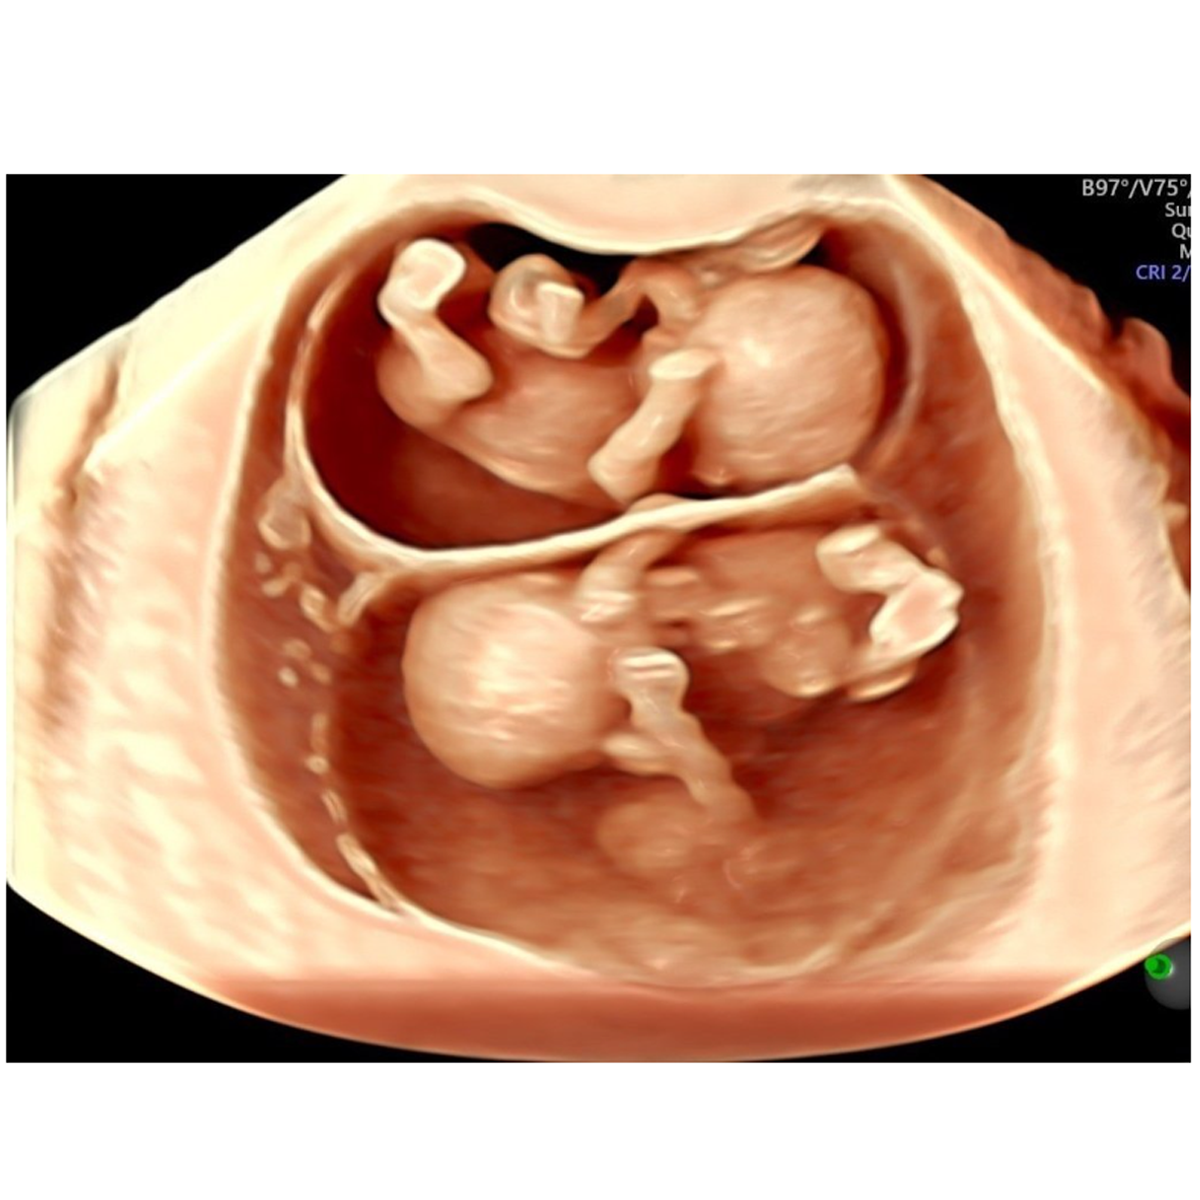

IX. Multiple Pregnancy Scan (Twins, Triplets and so on…):

If there is more than one baby, fetal growth needs to be checked every 4 weeks. There is a subset of multiple pregnancies, called monochorionic or monoamniotic type, they need more frequent scans, every 2 weeks or even more frequently, depending upon presence of any complications.